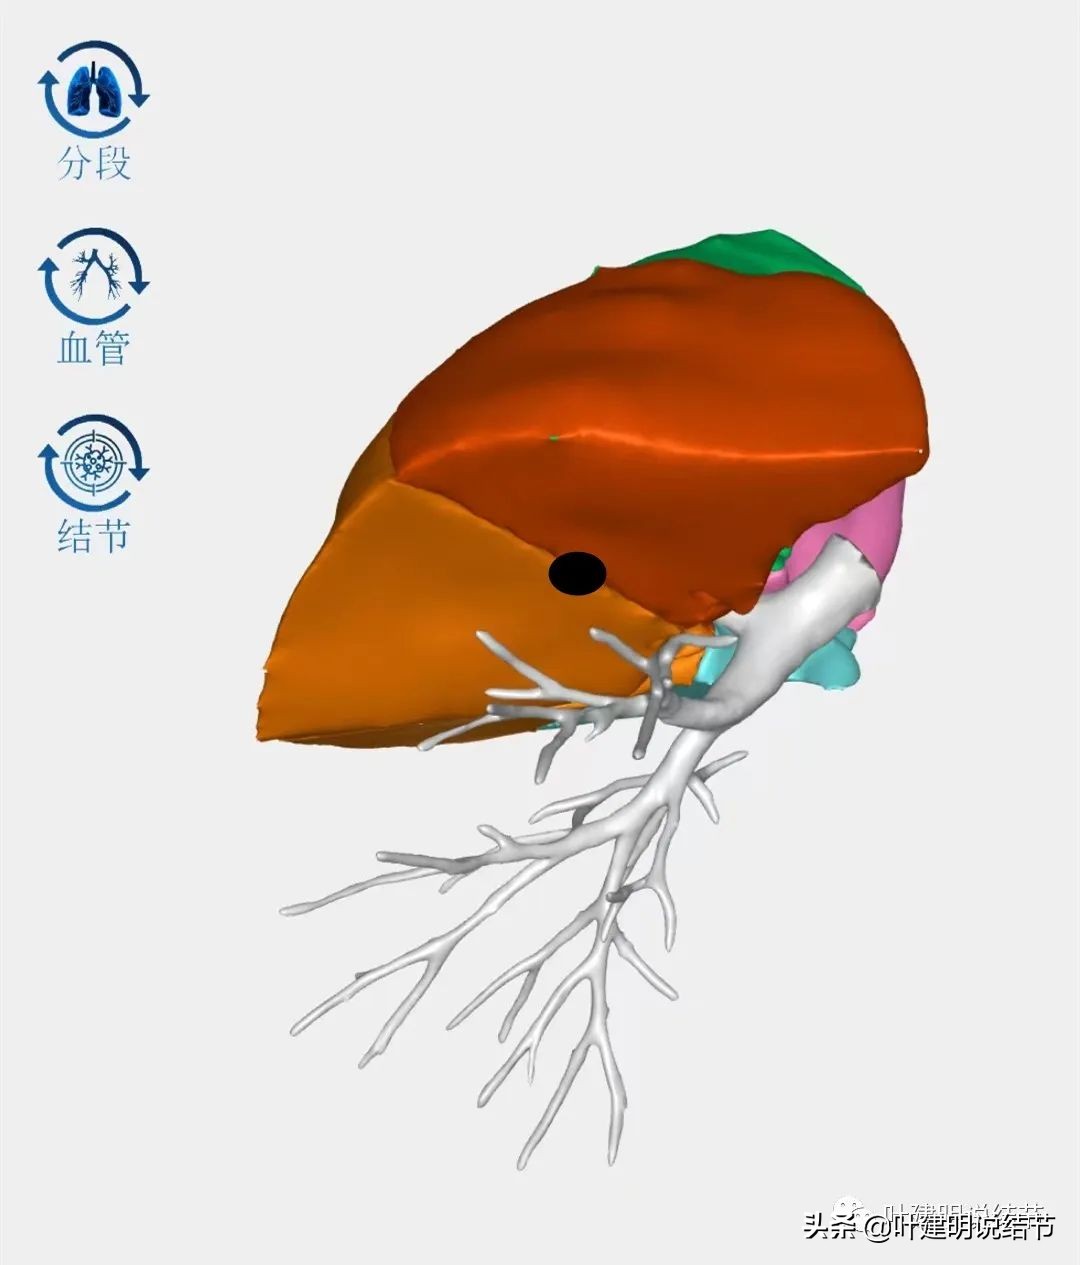

(一)上叶病灶的考虑:

上叶病灶在三维视角上应该是类似上图的位置,它近水平裂,但窝在上叶凹向肺实质中央去的地方,其实术中是很难上钳去钳夹的,因为钉子是直的,即使切割缝合器能转弯,但钉匣仍是直的,距离肺门部又太近,病灶又凹在那里是有困难的。而如果我先在结节的边缘附近缝一针,将病灶提起来,是不是就能更容易卵圆钳夹并放置切割缝合器钉匣呢?如下图: